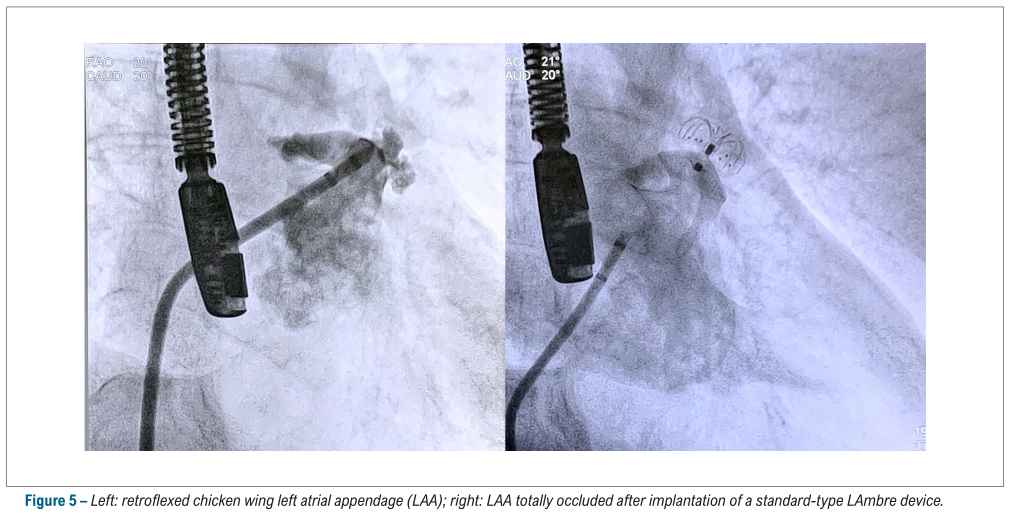

LAmbre™植入成功率为100%, 所有患者均无明显残余分流(> 5mm),仅4例患者(7.8%)在手术结束时存在较小残余分流(<5mm)。手术即刻并发症包含2例心包积液,1例器械栓塞(成功抓捕),未出现其他不良事件。此外,3位患者存在卵圆孔未闭(PFO),术者成功通过2例患者的PFO通道进入左心房实施封堵,另外一例患者心耳为反鸡翅形态,经PFO路径导致鞘管轴向不佳,最终改为实施房间隔穿刺进入左心房行封堵术。

LAmbre™术中影像